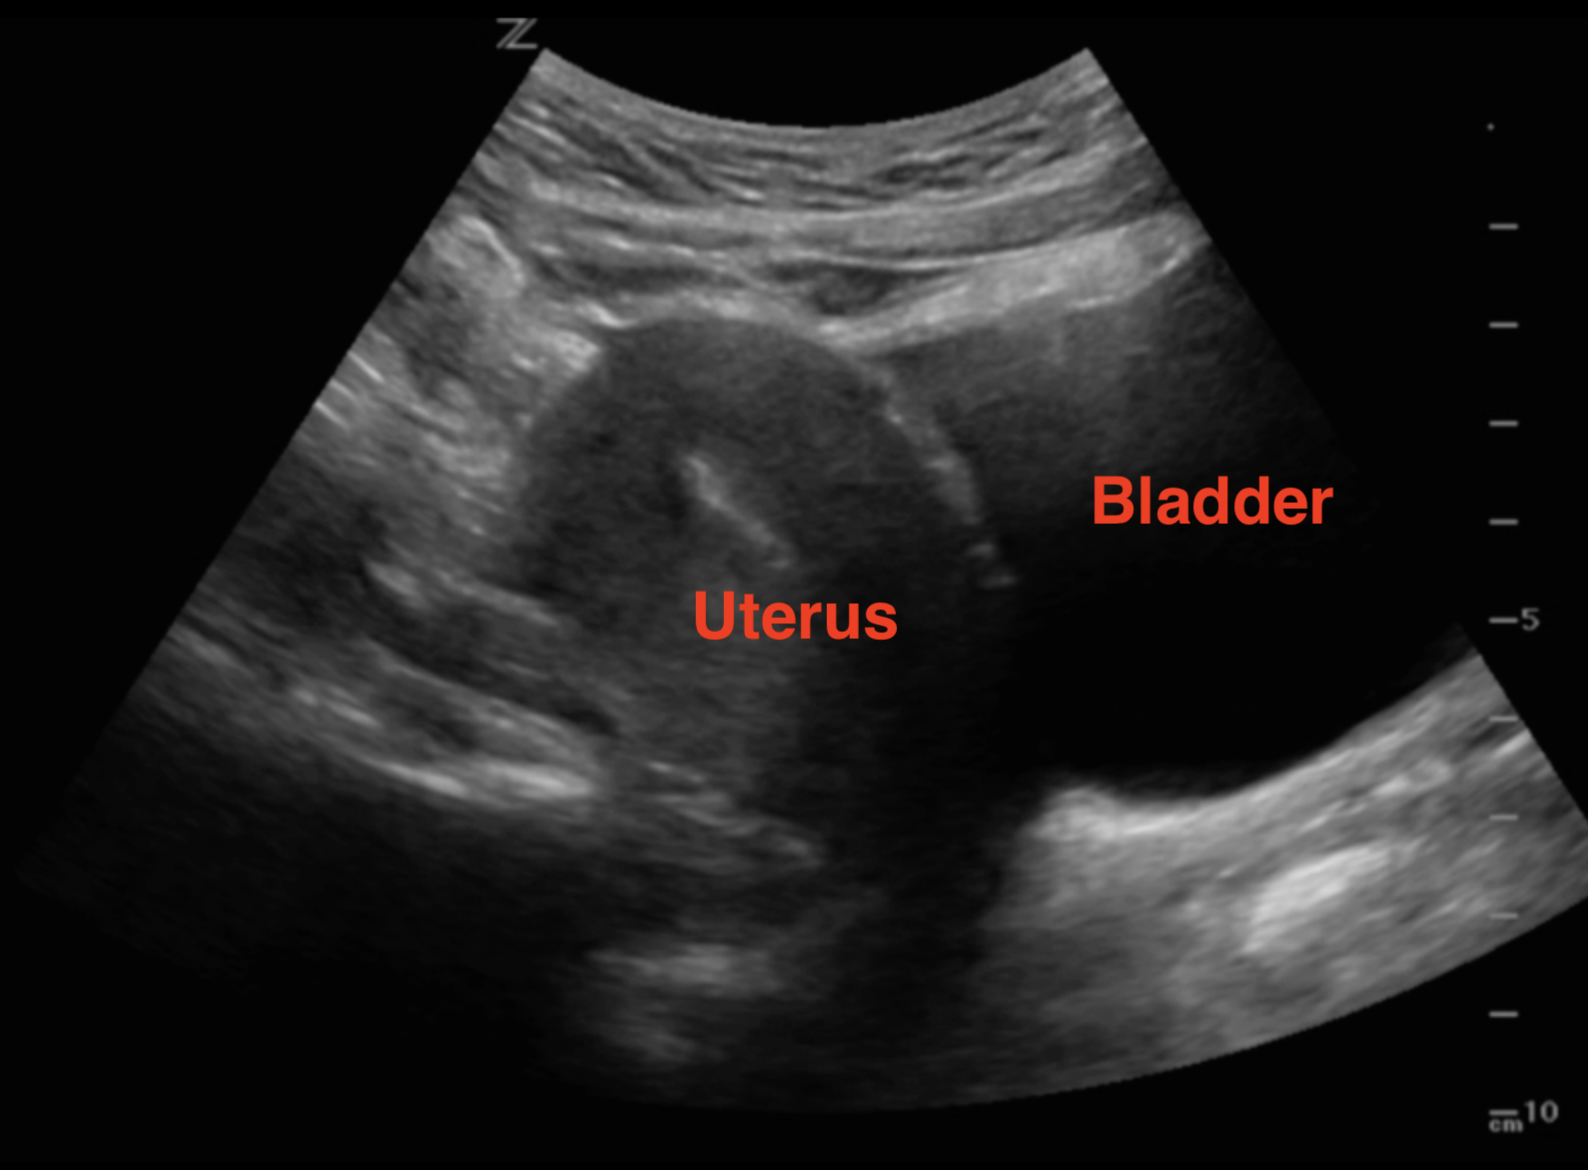

Ultrasound Case 046 LITFL POCUS Self Assessment Quiz

https://litfl.com/wp-content/uploads/2018/12/LITFL-Top-100-Ultrasound-46-02-6-weeks-pregnant.jpg